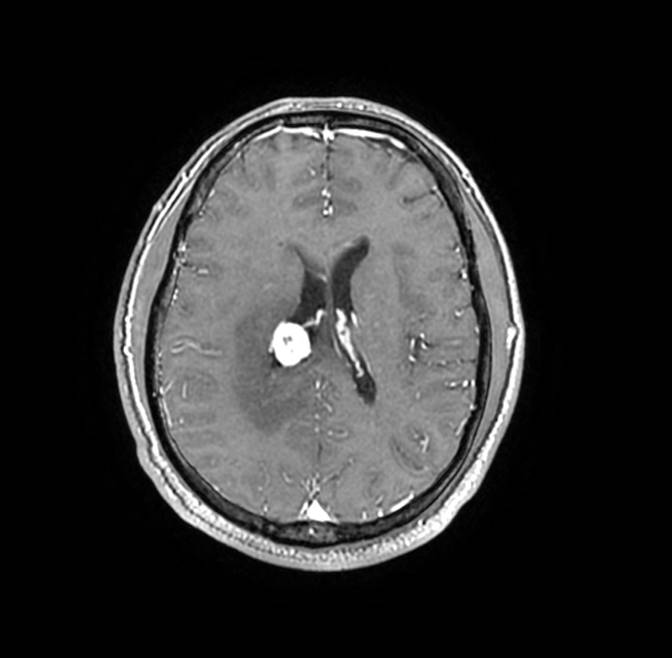

PET/CT檢查

影像診斷: 右側(cè)側(cè)腦室旁腦實(shí)質(zhì)內(nèi)結(jié)節(jié),代謝異常增高(SUVmax 12.13),伴瘤周水腫。

病理診斷:腦膜瘤二級(jí)

PET/CT鑒別診斷

正電子發(fā)射計(jì)算機(jī)斷層(positron emission tomography,PET)是一種分子成像技術(shù),PET 應(yīng)用 18F-FDG等顯像劑可顯示人體內(nèi)細(xì)胞、分子或者基因水平的生物學(xué)、病理學(xué)過(guò)程,進(jìn)一步實(shí)現(xiàn)疾病早期定量與定性診斷。PET/CT使形態(tài)影像學(xué)與功能影像學(xué)得到了良好的結(jié)合,更有利于對(duì)腦膜瘤進(jìn)行全面的評(píng)價(jià)。既往研究發(fā)現(xiàn),18F-DG PET/CT對(duì)診斷WHOⅠ、Ⅱ級(jí)腦膜瘤具有較高的敏感度,F(xiàn)DG攝取可用于評(píng)估腦膜瘤的腫瘤增殖情況,以此達(dá)到鑒別腦膜瘤的良、惡性的目的。有學(xué)者統(tǒng)計(jì),WHOⅡ、Ⅲ級(jí)與 WHOⅠ級(jí)的平均標(biāo)準(zhǔn)化攝取值(standardized uptake value,SUV)分別為 2.51 (1.36,3.66)和 0.42 (0.12,0.73),WHOⅡ、Ⅲ級(jí)腫瘤與正常組織比率(T/N比率)存在差異,WHOⅡ級(jí)腦膜瘤的 SUVmax和最大T/N比率顯著高于 WHOⅠ級(jí)腦膜瘤。SUV和T/N比率對(duì)高級(jí)別腦膜瘤的診斷有較高的特異度。

此例,PET/CT全身檢查不僅排除了轉(zhuǎn)移瘤的可能性,增高的SUV值無(wú)創(chuàng)地鑒別腦膜瘤的良惡性,充分體檢PET/CT大視野、形態(tài)與功能影像結(jié)合的優(yōu)勢(shì)。